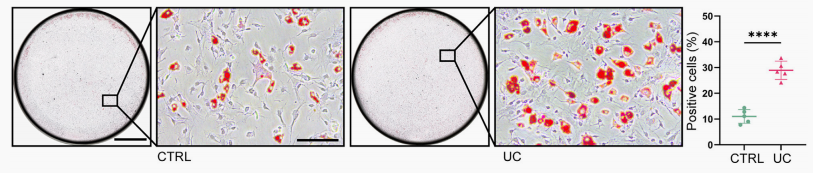

骨髓間充質干細胞成脂誘導后油紅O染色.png

骨髓間充質干細胞成脂誘導后油紅O染色